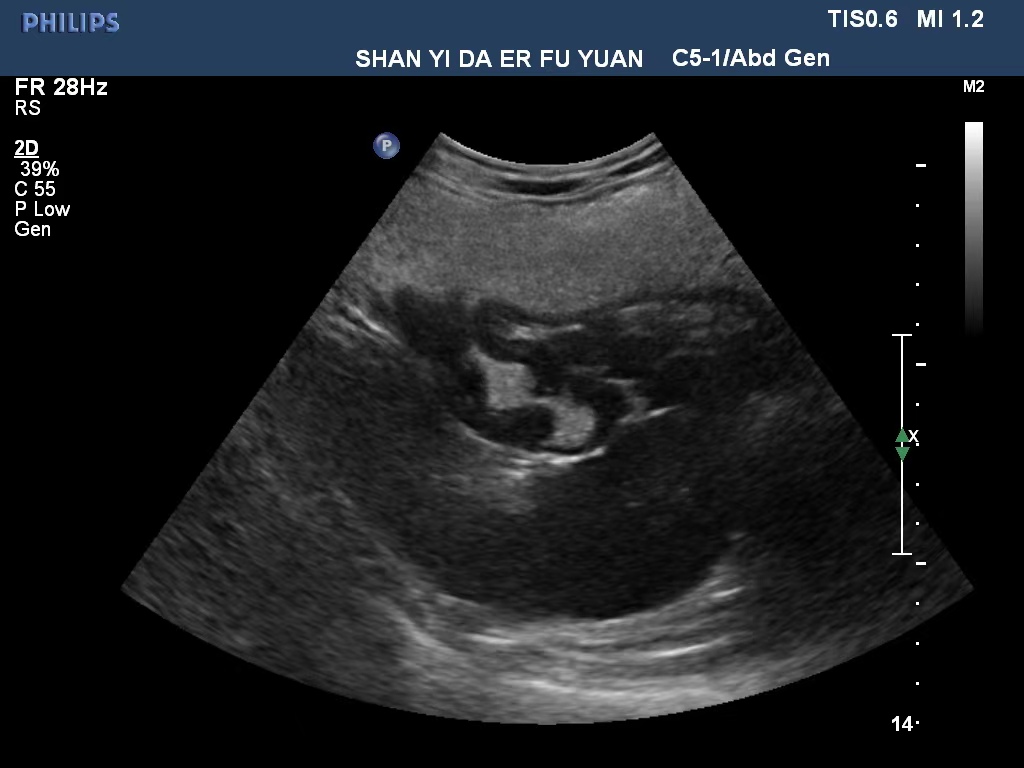

病例展示:

胃癌

胃息肉

胃內異物—磁力珠

胃潰瘍

急性胃炎